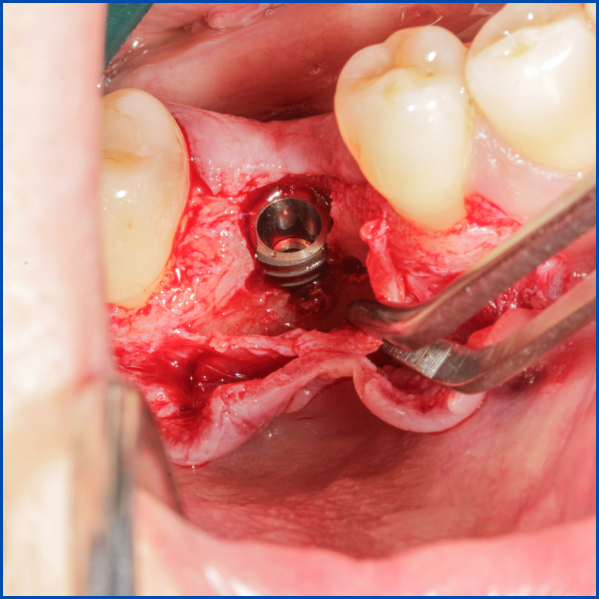

Kist nedeni ile çene kemiğinde defekt oluşmuş vakamıza sert ve yumuşak doku ogmentasyonu uyguladık.